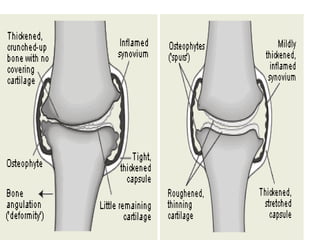

MORPHOLOGY

• Gross picture:

1) Granular, irregular articular cartilage as it

becomes soft due to degradation.

2) Eventually full thickness portions of cartilage

are sloughed exposing subchondral bones

which now become new articular surface.

3) Friction smoothens bony surfaces giving it

appearance of polished ivory (bone

eburnation).

4) Sclerosis of underlying bone.

• Fracture gaps allow synovial fluid to be

forced into subchondral regions resulting

in fibrous walled cysts.

• Mushroom shaped osteophytes (bony

outgrowths) develop at margins of

articular cartilage & are capped by

cartilage that gradually ossify.

• Synovium shows minor alterations & is

congested & fibrotic & may have scattered

ch. inflammatory cells.

• In severe cases, fibrous synovial pannus

is formed.

• JOINTS:

1): SYNOVIUM (gross) becomes edematous,

thickened, & hyperplastic.

2): Normal smooth contour is transformed→

formation of fronds & villi.

8): Pannus formation.

PANNUS : mass of synovium & synovial stroma

consisting of inflammatory cells, G.T, &

fibroblasts.

- Grows over articular cartilage & causes its

erosion.

- Pannus bridges the apposing bones forming

fibrous ankylosis which ossifies resulting in

bony ankylosis.